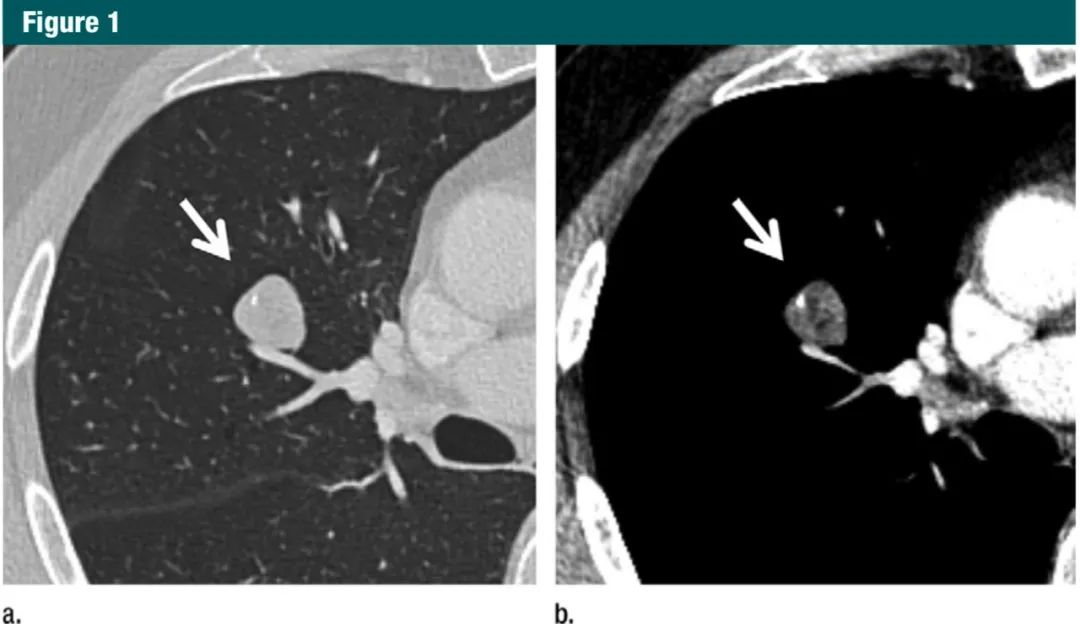

使用厚层观测病灶会增大平均体积,使小结节的特征显示不准确,对于部分实性形态和脂肪或钙化成分的结节,则会影响管理方案(图 1-3)。冠状位和矢状位序列能有助于区分结节和瘢痕(图 4)。这个建议并不局限于专门为结节评估或筛查肺癌而进行的检查,因为任何成人都有可能偶发肺结节。如果初次检查用的是厚层,为了对比,那么短期内还需要做薄层 CT 随访。

图1:(a)肺窗(b)纵隔窗:1mm层厚CT显示一个边界光滑的实性结节(箭头)、其内有脂肪和钙化成分,符合错构瘤。对于这种病灶,不建议进一步CT随访。7Gc帝国网站管理系统